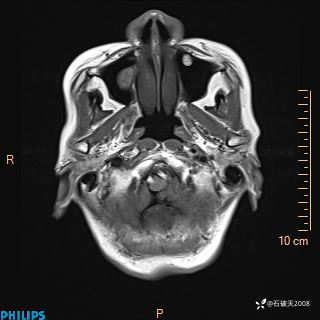

女 86岁 主 诉:乏力1月

现病史:患者1月前活动出现双下肢乏力,无头晕、头痛、恶心、呕吐、肢体活动不利,休息后缓解,间断断发作,症状进行性加重,在家口服药物治疗(具体不详),效差,为进一步诊治,来我院,门诊按“乏力”收住我科,患者自发病以来,神志清,精神稍差,饮食睡眠欠佳,大小便正常,体重未见明显改变。

T2